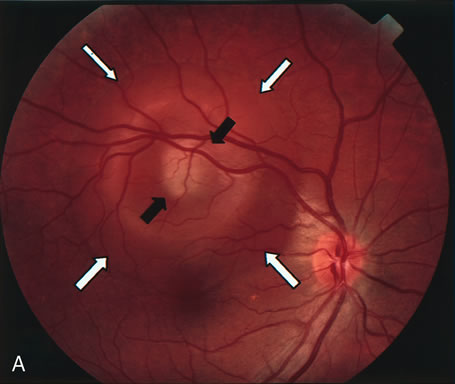

Fig. 14. A. Color photograph of the right eye shows a ramified pattern of choroidal vascular abnormality irradiating from the peripapillary area toward the macula. The dilated vascular channels end with bulging polyp-like structures. A larger, orange, saccular dilation is seen inferior to the macula (white arrow); leakage of fluid from this vascular abnormality results in serosanguineous pigment epithelium detachment (black arrows). B. The corresponding fluorescein angiogram composite highlights the vascular lesion in the peripapillary area and the serosanguineous detachment of the pigment epithelium that extends inferiorly and temporally off the macula.

PCV is characterized by the presence of dilated, choroidal vascular channels ending in orange bulging polyp-like dilations in the peripapillary and macular area. Associated features are recurrent subretinal hemorrhage and vitreous hemorrhage, relatively minimal fibrous scarring, absence of retinal vascular disease, pathologic myopia, and signs of intraocular inflammation. FA demonstrates the presence of the dilated vascular channel (Fig. 14 and 15). However, the presence of blood and exudation may block the details of the choroidal circulation on the angiogram. In these cases, ICG angiography can better demonstrate the presence of a distinct network of vessels within the choroid because the larger choroidal vessels are filled with dye.